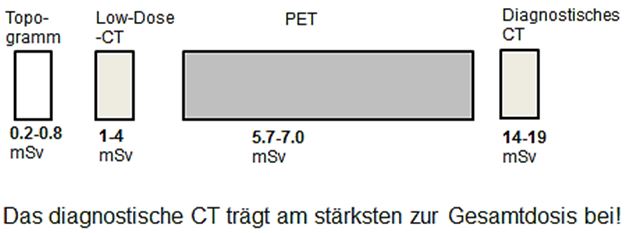

Überlegungen zur Reduzierung der Strahlenexposition:

Falls im Vorfeld der PET-CT Untersuchung eine CT-Schnittbilddiagnostik gelaufen ist, kann man auf das diagnostische CT bei der PET-Untersuchung verzichten. Die Low-Dose CT reicht völlig aus, um die PET-Bilder zu anatomischen Strukturen zuzuordnen.

Falls ein diagnostisches CT bei der PET-Untersuchung notwendig ist, kann man auf das Low-Dose CT verzichten, und das diagnostische CT zur Schwächungskorrektur heranziehen.